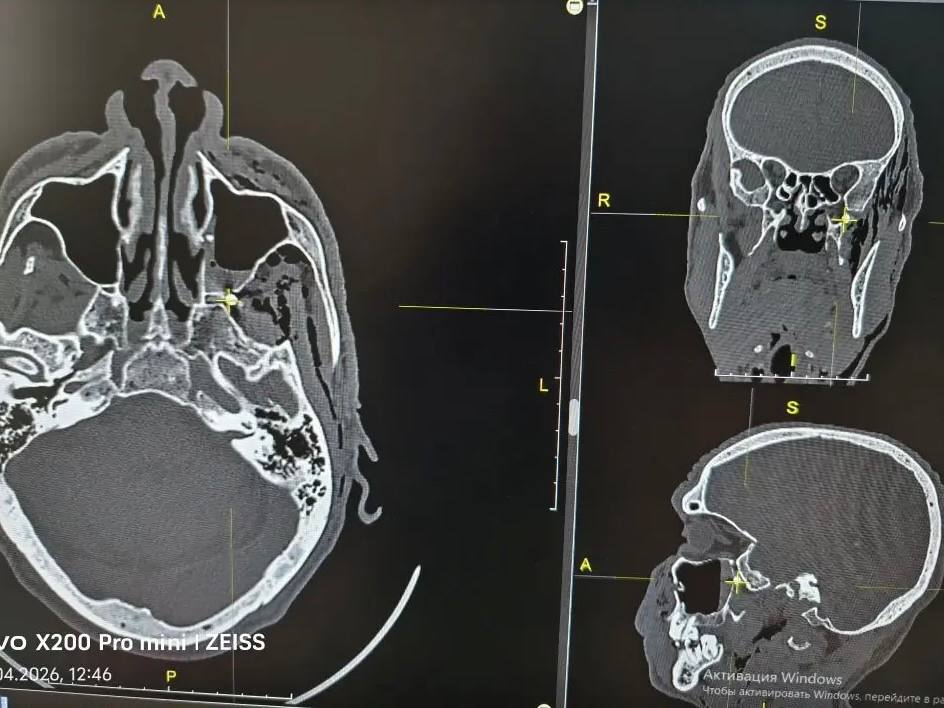

В городскую больницу Орска поступил мужчина, в которого на собственной даче выстрелил из пневматического оружия сосед. Ранение оказалось тяжёлым — пуля застряла в голове.

Обследование показало: инородное тело прошло сквозь переднюю и заднюю стенки верхнечелюстной пазухи и остановилось в крыло-нёбной ямке. Это небольшое, но крайне важное пространство за верхней челюстью, которое врачи называют «коммутационным узлом». Через него проходят нервы и сосуды, связывающие глазницу, нос, рот, глотку и область под скулой. Повреждение этой зоны грозит серьёзными последствиями.